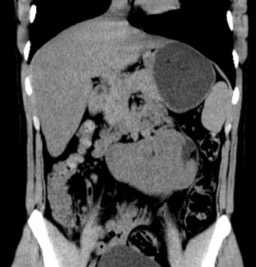

На представленных Т2-ВИ с жироподавлением определяются билатеральные кисты семенных пузырьков (а, аксиальная плоскость) и увеличение почек за счет множественных кист (б, фронтальная плоскость).